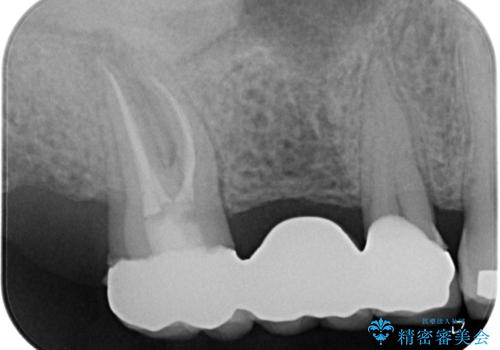

銀歯に隠れていて術前のレントゲンでははっきりと分かりませんでしたが、元々非常に大きなむし歯があったようで、銀歯の中で神経組織が壊死を起こしていました。

速やかに根管治療を行い、無事に痛みを取り除くことができました。